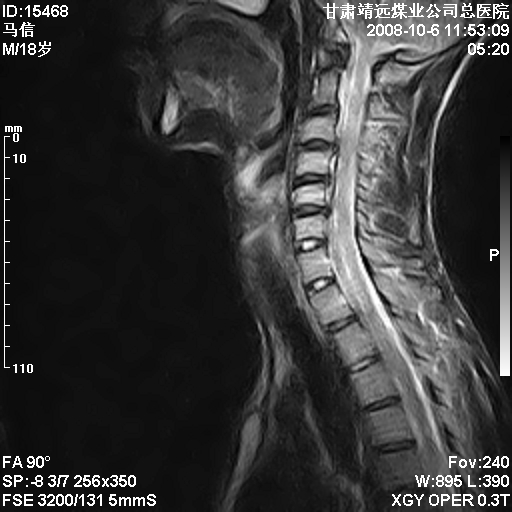

标题: MRI1827:颈椎内异常信号,是不是占位。

患者18岁,学生,在玩耍中受伤来检查,患者喜欢打篮球。颈椎内异常信号影,我们考虑占位,但是不像占位,又考虑硬膜囊的增厚,大家关建看颈椎椎管内的那个异常占位信号

腰椎的改变是不是正常发育的改变,还是打篮球的长期慢性损伤。

考虑 c3-4 c4-5 c5-6椎间盘突出,l3-4 l4-5 l5-s1椎间盘变性

后纵韧带增厚,颈2/3、3/4、4/5、5/6椎间盘变性、突出;椎体有旋转,提示椎小关节有问题;腰椎间盘变性,许莫氏结节。